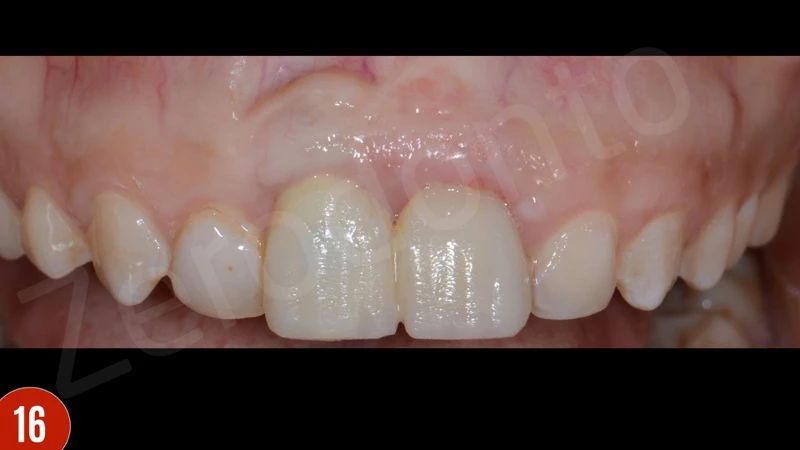

Sau khi gây tê tại chỗ, răng giả đã được cắt và loại bỏ. Sau đó, xương ổ răng vẫn hiện diện quanh implantl. Trong lần điều trị này, điều chỉnh chính xác abutment được thực hiện và xác nhận với X-quang. Khu vực cấy implant được để lành thương mô mềm. Sau 8 tuần lành thương mô mềm, phẫu thuật ghép mô liên kết (CTG) đã được lên kế hoạch với vạt bao, vạt nhú lợi xoay xiên (oblique rotated papilla flap) bằng cách sử dụng các đường rạch dưới lợi viền. Kĩ thuật chia tách tạo khả năng di động thích hợp cho vạt niêm mạc. Các phần lợi viền phía cổ được loại bỏ. CTG được lấy bằng kỹ thuật loại bỏ biểu mô. Để bù đắp thiếu hụt niêm mạc, CTG được gấp đôi và khâu bằng với vật liệu tự tiêu trước khi khâu cố định. CTG đã được cố định mặt môi, ôm lấy bề mặt abutment. Vạt niêm mạc tự do, thụ động, căng được khâu.

Sự lành thương sớm và tăng độ dày niêm mạc phía môi là thích hợp. Ba tháng sau khi phẫu thuật nha chu, bệnh nhân báo cáo có lỗ rò ở vùng đỉnh răng 21. Đo độ sâu thăm khám là 2-3 mm. Do răng không vừa khít, và lực nhai quá mức, một gãy xương ở vùng chóp đã gặp phải. Bệnh nhân được giải thích cần nhổ răng. Bệnh nhân đã quyết định cấy ghép tức thì.